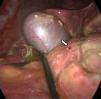

Hombre de 29 años con dolor abdominal de 48 h de evolución. El interrogatorio clínico, la exploración física y los hallazgos radiológicos fueron compatibles con apendicitis aguda complicada (fig. 1). Durante la laparoscopia se diagnosticó síndrome de Valentino (figs. 2 y 3). Se realizó apendicectomía, cierre primario con parche de Graham, toma de biopsia, lavado de cavidad y colocación de drenajes vía laparoscópica, con adecuada evolución posquirúrgica. En el nuevo análisis de la placa simple de abdomen se observó aire libre subdiafragmático (fig. 4).